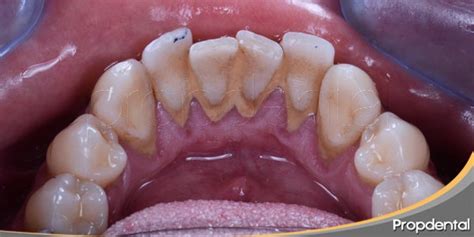

El sarro dental, también llamado cálculo dental, es una placa bacteriana que se ha endurecido debido a los minerales presentes en la saliva. Todo comienza con la placa dental, una película transparente y pegajosa que se forma constantemente en nuestros dientes. Si no se elimina correctamente (con un buen cepillado y el uso de hilo dental), esta placa se mineraliza y se convierte en sarro, especialmente en zonas como detrás de los dientes inferiores.